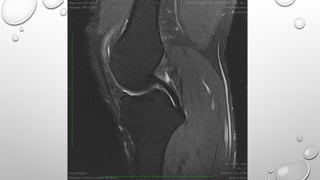

• MENISCAL AND CARTILAGE MAPPING

• THEY AREGENERALLY USED TO CREATE T2* WEIGHTING IMAGES IN VERY SHORT SCAN TIME THEY ARE USED IN • MR ANGIOGRAPHY • MR MYELOGRAPHY • SWI • MENISCAL AND CARTILAGE MAPPING DISADAVANATGE : SENSITIVE TO FLOW AND MOTION SIEMENS SEQUENCE: FISP